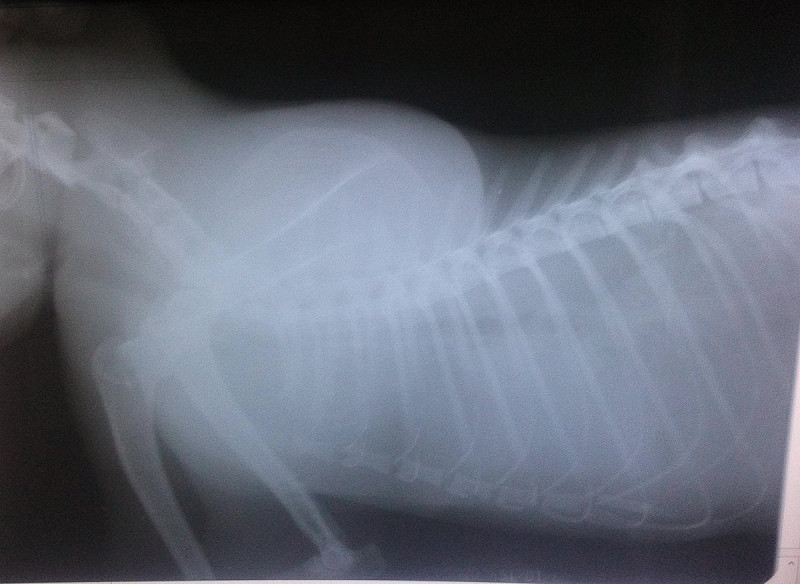

В клинике собаке сделают рентген, который подтвердит или опровергнет отек легких, а также проведут осмотр собаки, прослушают ее и выполнят ряд лабораторных исследований.

Для диагностики отека легких у собак используются такие методы, как аускультация, рентгенография грудной клетки или ультразвуковое исследование, также требуется анализ крови. Электрокардиограмма, анализ мочи и измерение кровяного давления — другие важные тесты, позволяющие выяснить, есть ли у вашей собаки отек легких.

Если состояние вашего питомца стабильное, можно выполнить рентгенографию грудной клетки, положив собаку на спину. На этой рентгенограмме могут быть признаки отека легких, такие как повышенная интерстициальная или альвеолярная непрозрачность. У собак, страдающих кардиогенным отеком легких, также могут наблюдаться кардиомегалия и расширенные легочные вены.

Рентгеновские снимки являются основным инструментом для диагностики отека легких, поскольку они выявляют жидкость внутри легких собаки. Рентген также может выявить увеличенное сердце или другие аномалии сердечной мышцы.